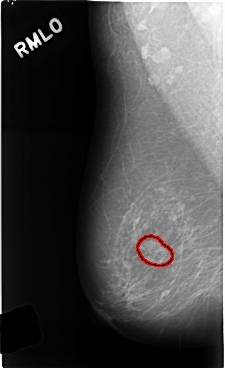

FILE: C_0454_1.RIGHT_MLO.OVERLAY

TOTAL_ABNORMALITIES 1

ABNORMALITY 1

LESION_TYPE MASS SHAPE LOBULATED MARGINS CIRCUMSCRIBED

ASSESSMENT 3

SUBTLETY 4

PATHOLOGY BENIGN_WITHOUT_CALLBACK

TOTAL_OUTLINES 1

BOUNDARY

RIGHT_MLO LINES 4784 PIXELS_PER_LINE 2920 BITS_PER_PIXEL 12 RESOLUTION 50 OVERLAY